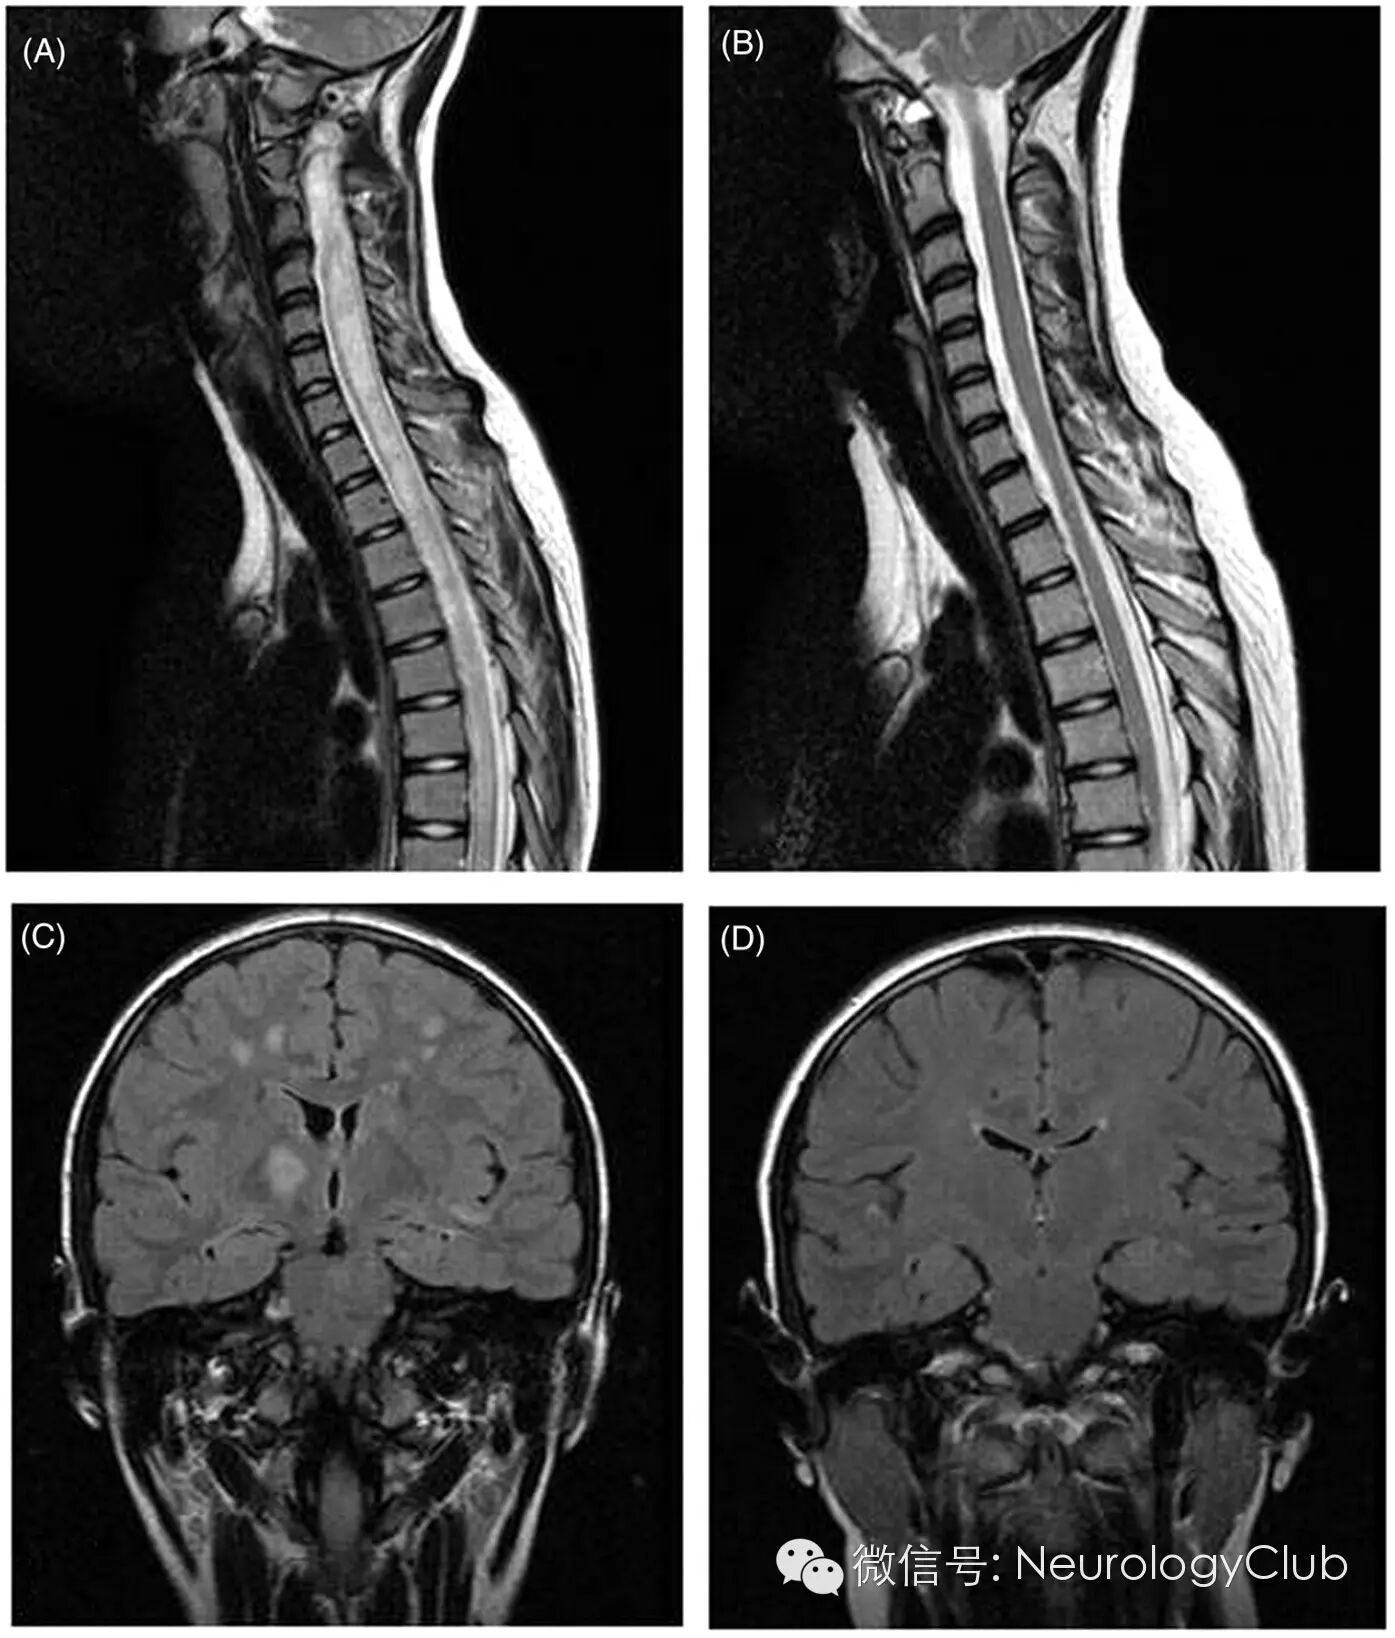

2急性播散性脑脊髓炎

(A:矢状位T2WI提示急性期脊髓长节段T2高信号;B:3月后复查病灶明显消失;C:冠状位FLAIR提示脑室旁,皮质下白质以及基底节区多发T2高信号;D:3月后复查病灶明显消失)